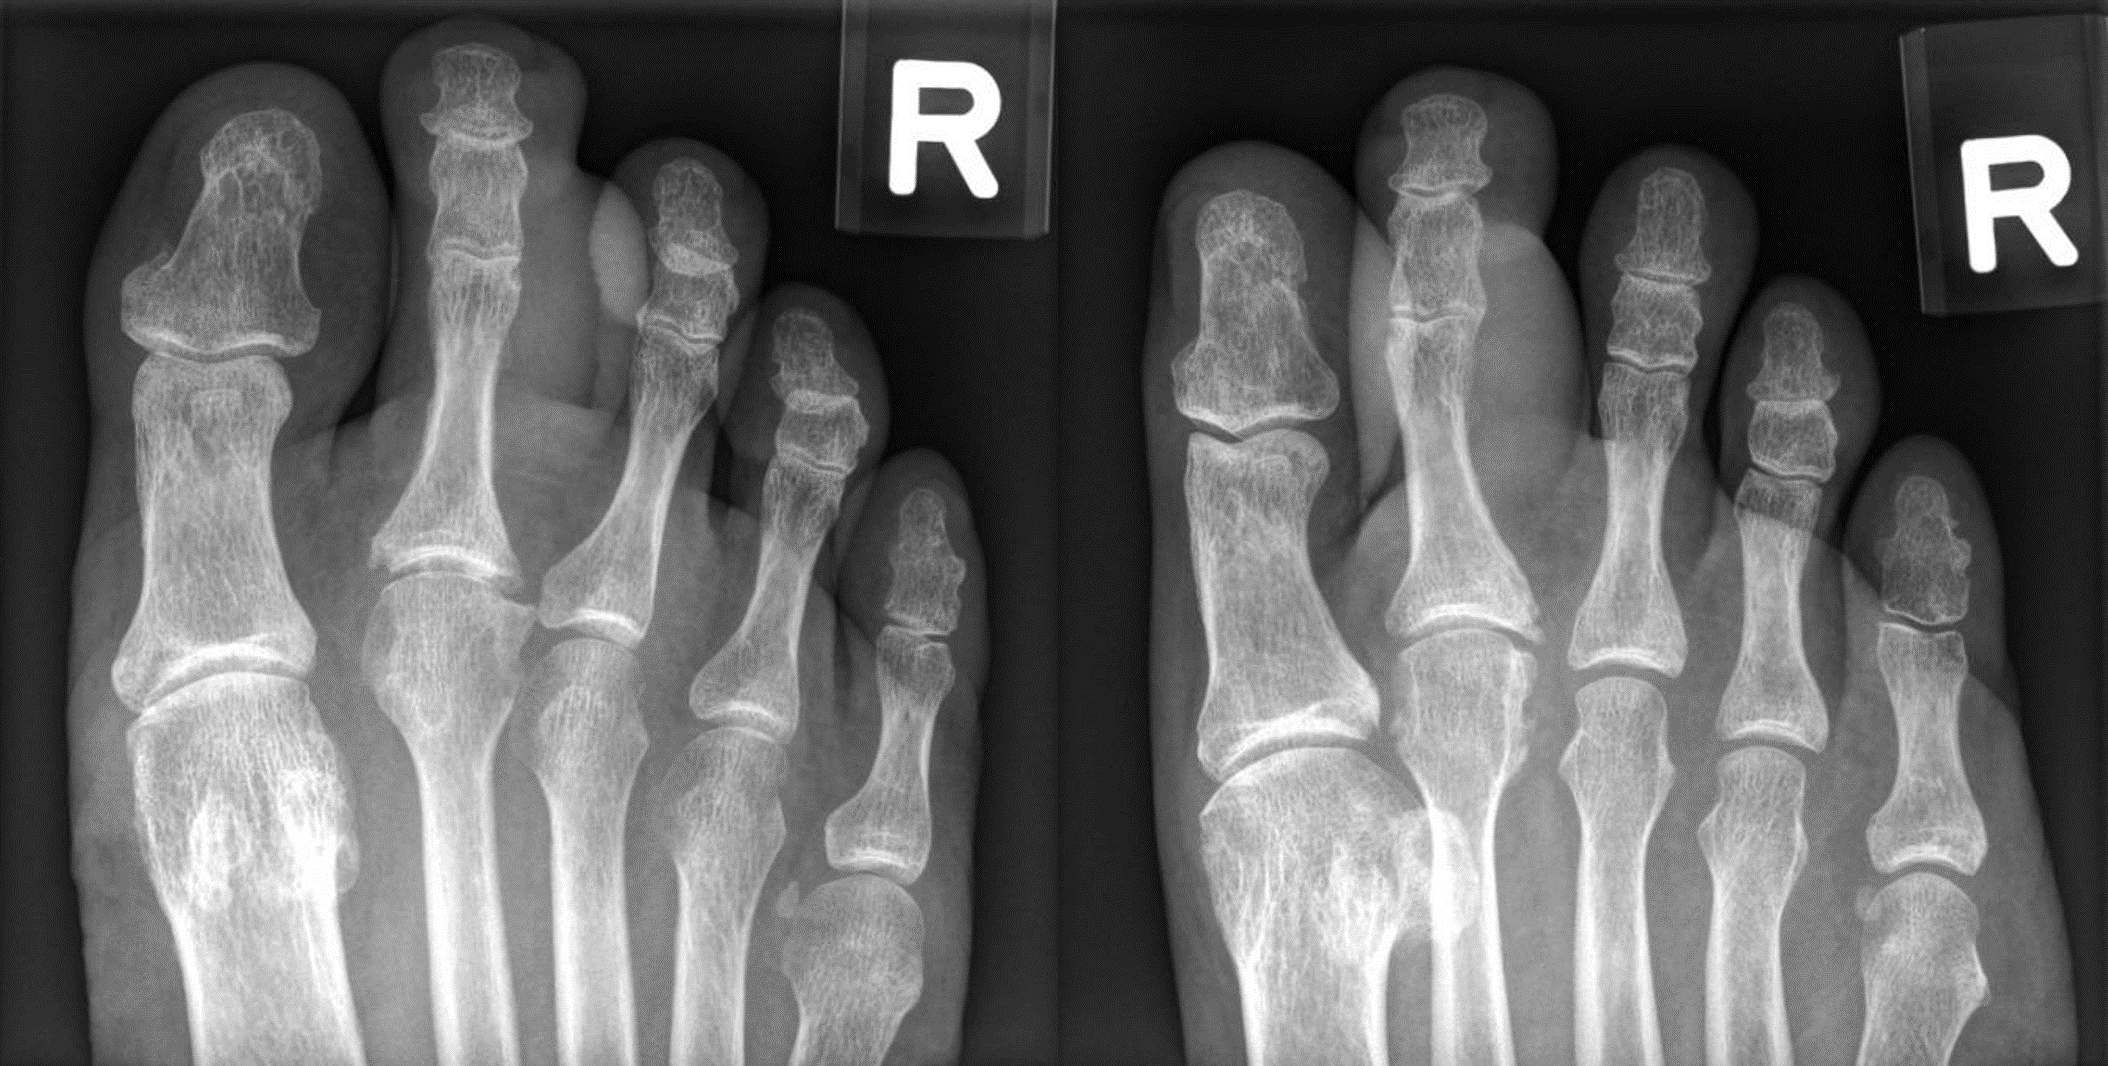

Initial investigations revealed raised inflammatory markers (TW 21.7 × 109/L, CRP 71.7 mg/L, ESR 45 mm/h) associated with hyperuricemia (9.9 mg/dL). A radiograph over the toes (Figure 1) showed gross soft tissue swelling over the right second toe and very small juxta-articular cortical erosions with sclerotic margins at the base and head of the right second proximal phalanx and head of right second toe metatarsal.